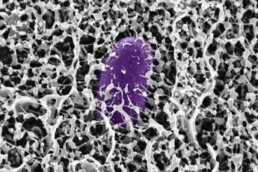

Scoperta del MIT: il muco contiene molecole che bloccano l'infezione da Salmonella

(Adnkronos) - Il muco, spesso ridotto a semplice sostanza appiccicosa, nasconde un sofisticato arsenale di molecole protettive. Una nuova ricerca condotta dai ricercatori del Massachusetts Institute of Technology (MIT) ha identificato come specifiche molecole chiamate mucine siano in grado di difendere l’organismo dalla Salmonella e da altri batteri responsabili di malattie diarroiche.

Lo studio, pubblicato sulla rivista Cell Reports, non si limita a identificare il meccanismo di difesa, ma apre concrete prospettive per lo sviluppo di mucine sintetiche da utilizzare nel trattamento o nella prevenzione di malattie di origine alimentare. Questo approccio potrebbe offrire una soluzione a basso costo a una sfida sanitaria globale che genera miliardi di costi annuali in tutto il mondo. La ricerca si è concentrata sulla MUC2, una mucina tipicamente presente nell’intestino. Le mucine sono polimeri a forma di spazzola, composti da complesse molecole di zuccheri (glicani) legate a una spina dorsale peptidica.

I ricercatori hanno scoperto che quando la Salmonella enterica viene esposta alla mucina MUC2, il batterio interrompe la produzione delle proteine codificate sull'”isola di patogenicità 1” (Salmonella pathogenicity island 1, SPI-1), essenziali per il sistema di secrezione di tipo 3 (T3SS) che permette al batterio di infettare le cellule ospite. Ulteriori analisi hanno rivelato che la MUC2 raggiunge questo risultato disattivando una proteina batterica di regolazione cruciale, nota come HilD. Bloccando questa proteina, la mucina impedisce l'attivazione dei geni T3SS. Utilizzando simulazioni computazionali, è stato dimostrato che alcuni monosaccaridi, come GlcNAc e GalNAc, possono legarsi al sito attivo della proteina HilD. Tuttavia, lo spegnimento dei geni avviene solo quando questi glicani sono ancorati alla spina dorsale peptidica della mucina. Lo studio ha inoltre rivelato che una mucina simile, la MUC5AC, presente nello stomaco, condivide questa capacità. I ricercatori dell'MIT, guidati da Katharina Ribbeck, Andrew and Erna Viterbi Professor of Biological Engineering e autrice senior dello studio, intendono ora esplorare l'uso di versioni sintetiche di queste molecole per potenziare le difese naturali del tratto gastrointestinale.

La dottoressa Ribbeck ha espresso l'obiettivo strategico della ricerca: “Utilizzando e riformulando questo motivo dal sistema immunitario innato naturale, speriamo di sviluppare strategie per prevenire la diarrea prima ancora che inizi. Questo approccio potrebbe fornire una soluzione a basso costo a una grande sfida sanitaria globale che costa miliardi ogni anno in perdita di produttività, spese sanitarie e sofferenza umana”.

Una delle applicazioni più promettenti per le mucine sintetiche è la profilassi pre-esposizione. Queste molecole potrebbero essere incorporate in compresse masticabili o in sali per la reidratazione orale, da consumare prima di recarsi in aree endemiche per la Salmonella o altre malattie diarroiche comuni.

Come ha spiegato la ricercatrice Kelsey Wheeler, co-autrice principale dello studio: “I mimic della mucina brillerebbero in particolare come preventivi, perché è così che il corpo ha evoluto il muco, come parte di questo sistema immunitario innato per prevenire l'infezione”. La strategia si basa sull'idea di rafforzare le barriere mucose nelle aree del tratto gastrointestinale che la Salmonella tende a infettare. La ricerca è stata sostenuta da diversi enti, tra cui l'U.S. Army Research Office, l'U.S. National Science Foundation e il National Institutes of Health. Immagine di cover per gentile concessione dei ricercatori del MIT ---tecnologiawebinfo@adnkronos.com (Web Info)